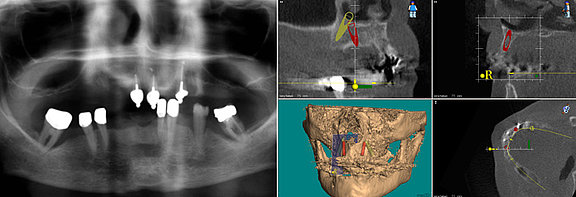

Questa radiografia di un paziente prima dell’intervento mostra le „zone calde“ di una procedura implantologica: in rosso sono evidenziati i seni mascellari e il nervo sensorio del labbro inferiore che attraversa la mandibola.

A causa di queste strutture anatomiche, che non devono essere lese, la quantità di osso disponibile al di sotto del seno mascellare o al di sopra del nervo sensorio mandibolare risulta spesso fortemente ridotta. Per questo motivo, nella porzione posteriore dei mascellari è spesso impossibile effettuare un impianto di tipo tradizionale senza una ricostruzione ossea preventiva (innesto osseo).

La radiografia (a sinistra) ha evidenziato – come previsto – un chiaro riassorbimento osseo a livello del mascellare superiore. Grazie alla tomografia computerizzata (TAC) eseguita (a destra) si è potuto analizzare un‘immagine tridimensionale dell’osso residuo e procedere alla pianificazione virtuale dell’intervento di implantologia. In questo modo si è potuto stabilire che la mascella aveva dimensioni sufficienti per accogliere i quattro impianti richiesti dal metodo All-On-Four.